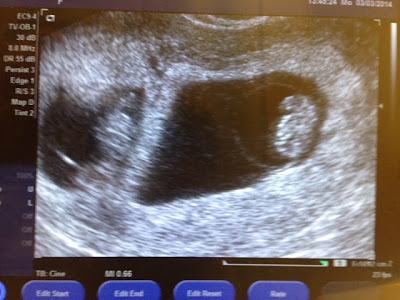

9 Weeks Today!